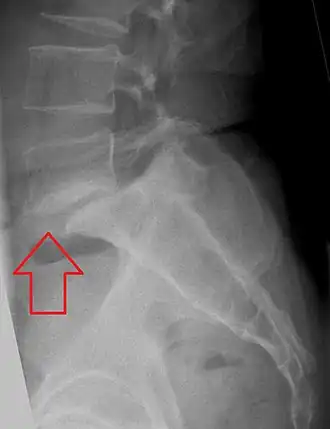

Anterolistesis L5/S1 -

Anterolistesis L5/S1